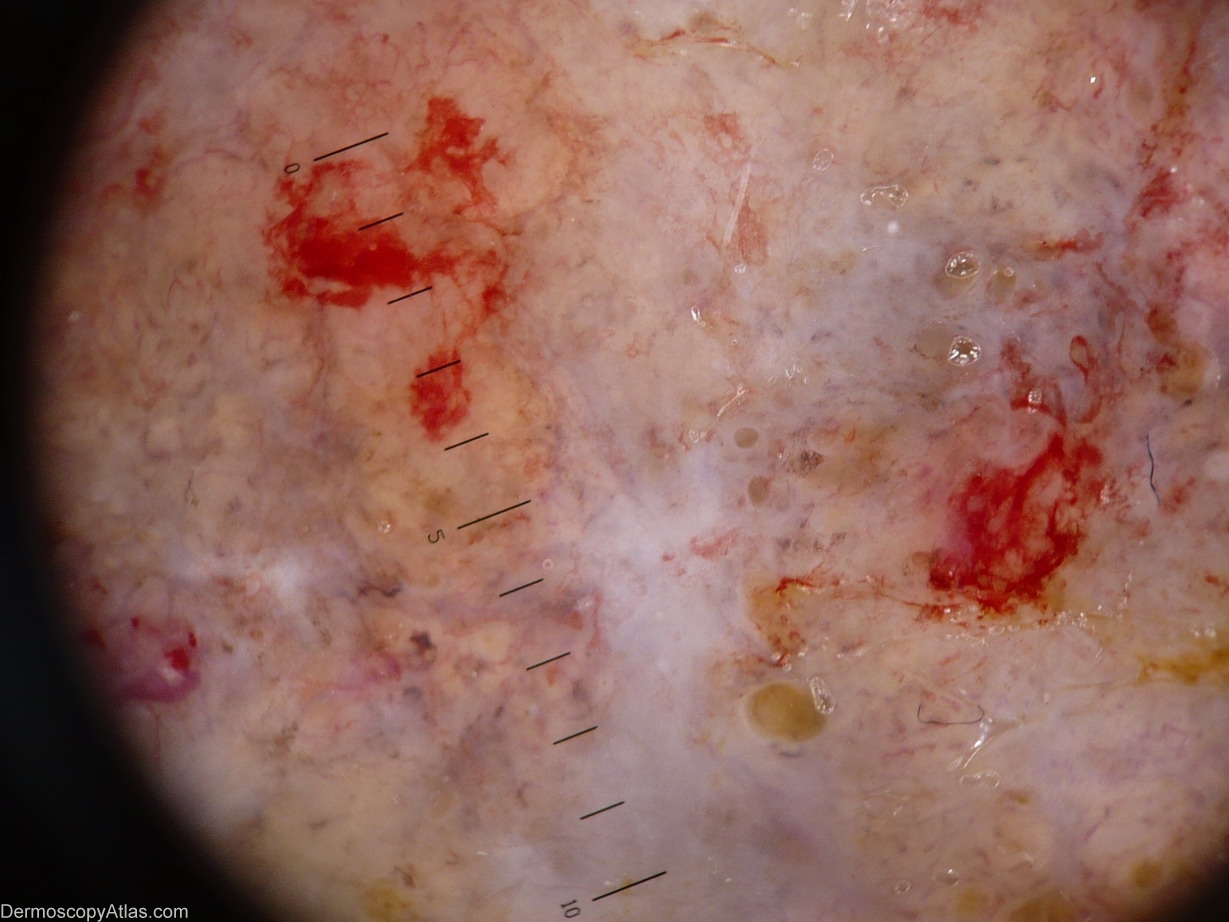

Dermoscopic description:Blue-white structures, polymorphous vessels(Corkscrew vessels), ulceration.

Site: Breast

Diagnosis: Melanoma metastases

A 26 year old woman with a history of nodular melanoma 8-12 months ago on her back. 2-3 months ago rapidly developed metastatic tumor on her breast. The woman live in a small village in Siberia and visited her doctor in town yesterday for the first time.